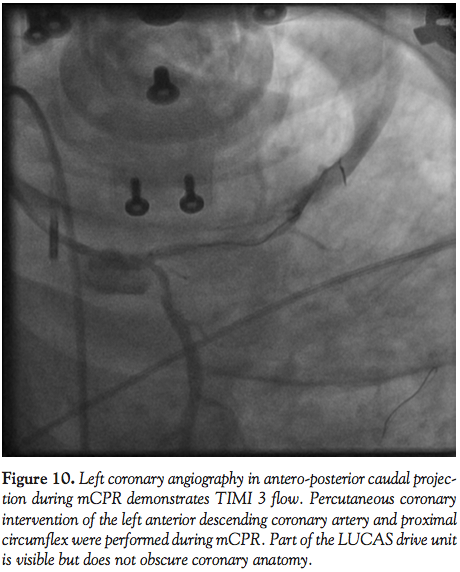

Case 5. A 57-year-old female with a history of diabetes mellitus, hypertension, and hyperlipidemia presented with a 3-month history of exertional angina. A diagnostic angiogram demonstrated a calcified 80% lesion in the mid left anterior descending (LAD) artery and 70% proximal circumflex lesion. The patient was referred to our institution for PCI. Her PCI was complicated by stent embolization and dissection of the proximal LAD and circumflex. The patient developed severe chest pain and angiography demonstrated TIMI 1 flow in the

LAD (Figure 9). The patient suffered cardiac arrest with recurrent ventricular fibrillation requiring defibrillation 15 times. Mechanical CPR was initiated and continued during 30 minutes of persistent cardiac arrest while an IABP was placed and PCI of the LAD and circumflex were performed (Figure 10). TIMI 3 flow was achieved after placing 2 drug-eluting stents from the proximal to mid LAD and an additional stent in the circumflex. The patient regained spontaneous circulation with minimal pressor support and she was transferred to the CCU. Her condition improved and both the vasopressor and IABP were discontinued the following day. On hospital day 4, the patient was discharged home without any sequelae.

In animal models, cerebral blood flow during CPR is improved with mCPR,15 and mCPR devices provide significantly higher coronary perfusion pressures than manual CPR.16 Coronary flow assessment has been reported in both animal models and human subjects.16,17 In 4 out of 6 patients studied by Larsen et al with TIMI 3 flow during mCPR, invasive measurements documented adequate coronary perfusion pressure gradients. In the present experience, coronary flow during mCPR is pulsatile, but classification by TIMI grade is readily apparent. In Cases 1, 4, and 5, the PCI procedure itself was performed during mCPR compressions (Figures 1, 2, 8, and 10).